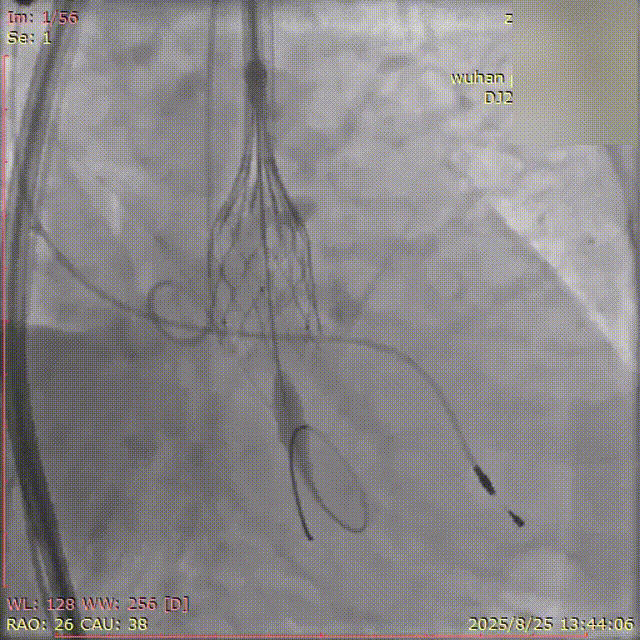

初始造影确定无冠窦

瓣膜释放过程(可见窦部扭转带来的异常轴向)

完全释放瓣膜左右重叠下评估位置

左冠切线位下立体评估左冠深浅

瓣膜脱钩